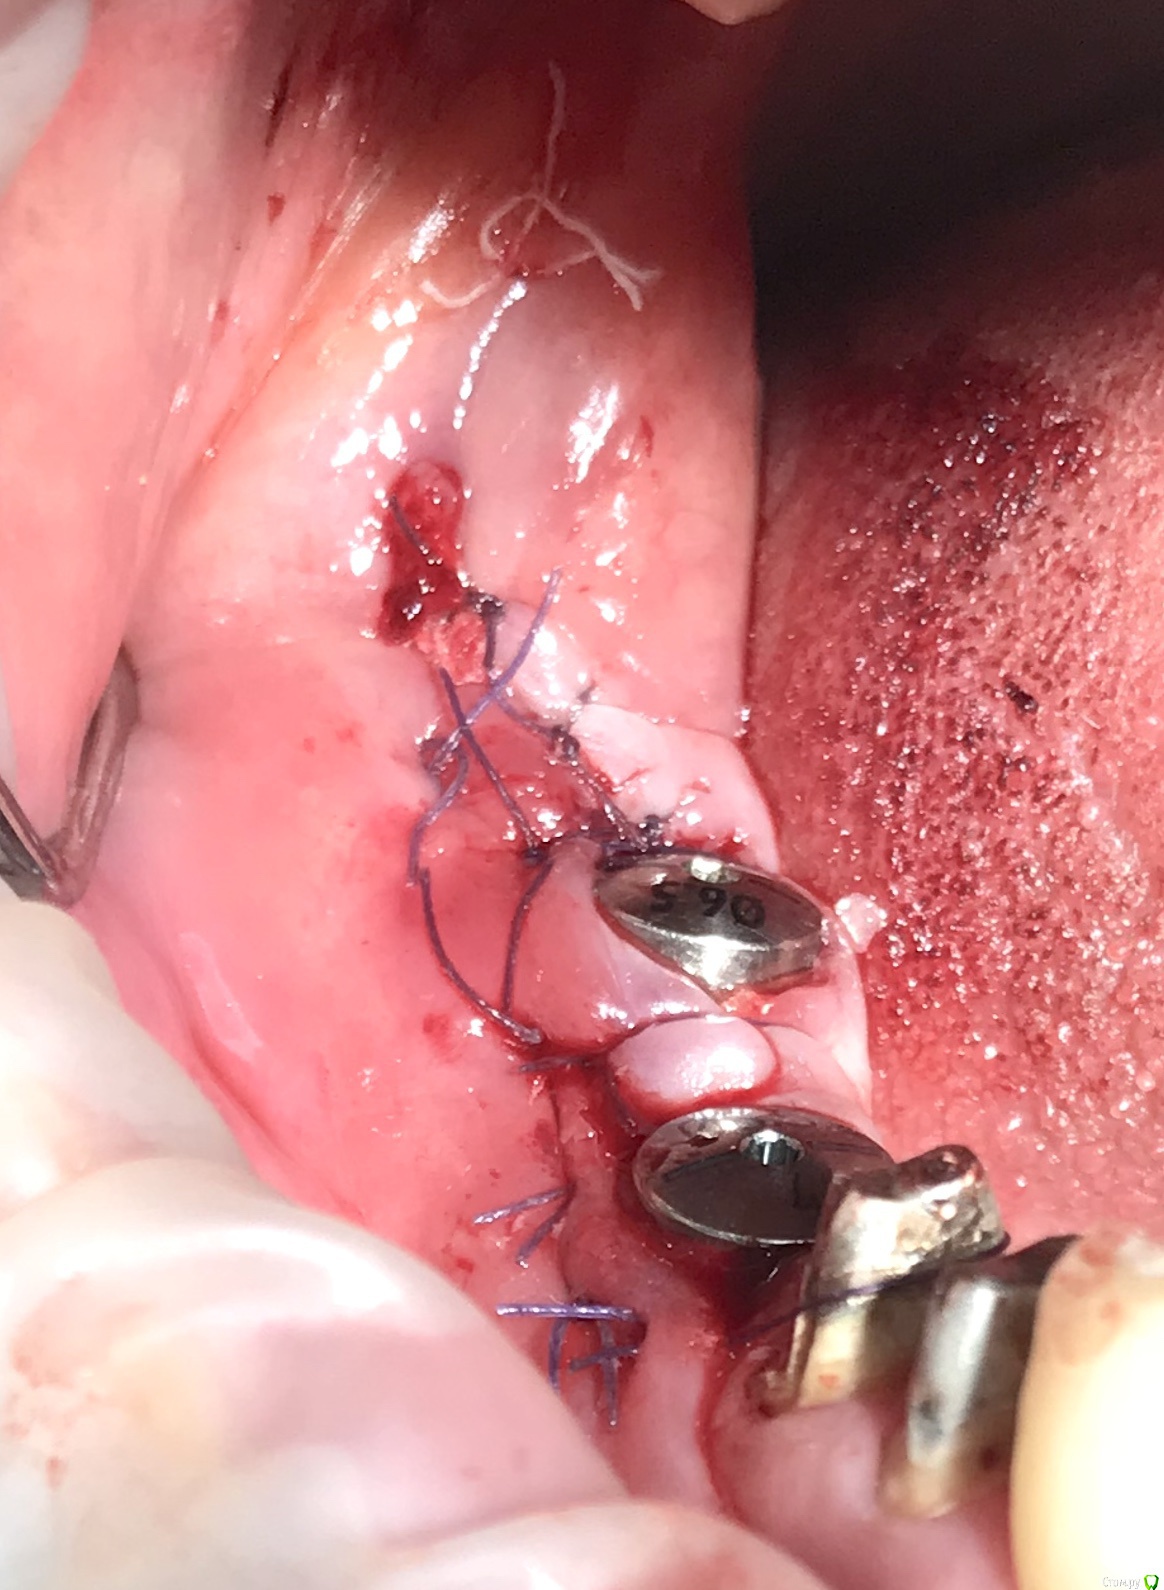

колесников Опубликовано 11 августа, 2019 Автор Поделиться Опубликовано 11 августа, 2019 (изменено) Что-то давно не ходил я ретромолярно. В данном случае лоскут использован не для закрытия лунки,а был перекинут Вестибулярно для десневого каркаса. Изменено 11 августа, 2019 пользователем колесников 4 Ссылка на комментарий

колесников Опубликовано 11 августа, 2019 Автор Поделиться Опубликовано 11 августа, 2019 Это из темы перекрытия лунки 8ки ретромолярноязычным лоскутом. Лучше на ножке,тк это не бугор,свободный лоскут из этой зоны выживает плохо Ссылка на комментарий